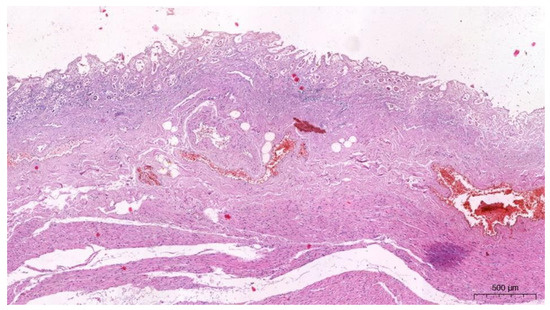

2.2.3. The Microscopic Examinations